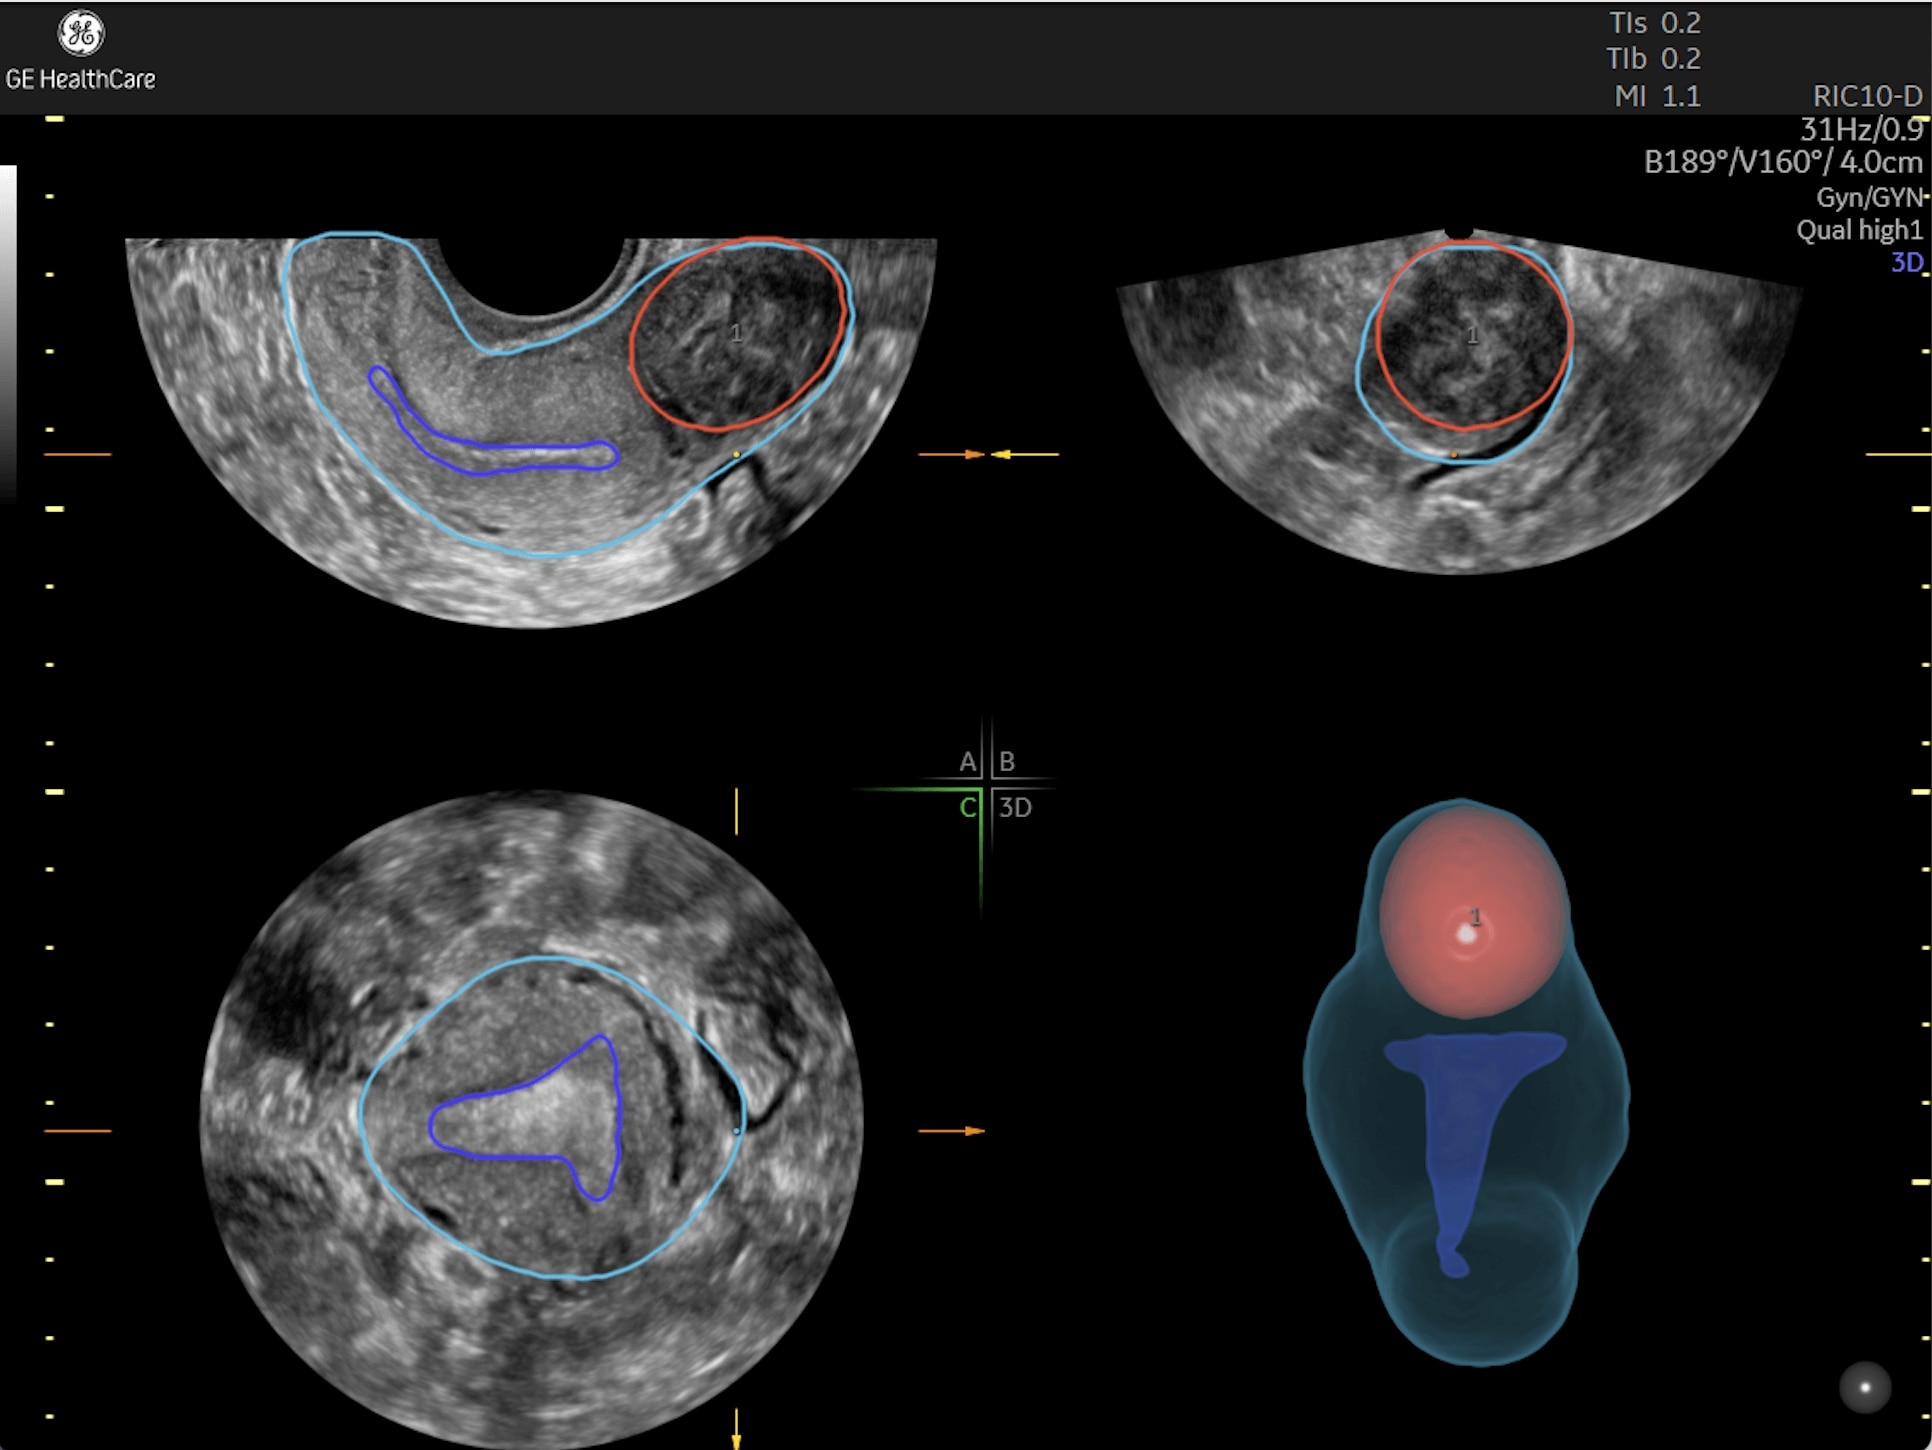

Generate spectacular 2D/3D and color Doppler images with increased penetration and stunning clarity, to help visualize critical details needed for diagnostic assurance. The Lyric Architecture unlocks new imaging and processing power to expand your imaging capabilities for years to come

Experience a new level of efficiency with the highly intuitive and customizable ultrasound that promotes progress and productivity. Leverage the power of artificial intelligence and easy-to-use automation tools that streamline workflows and make a real impact every day.